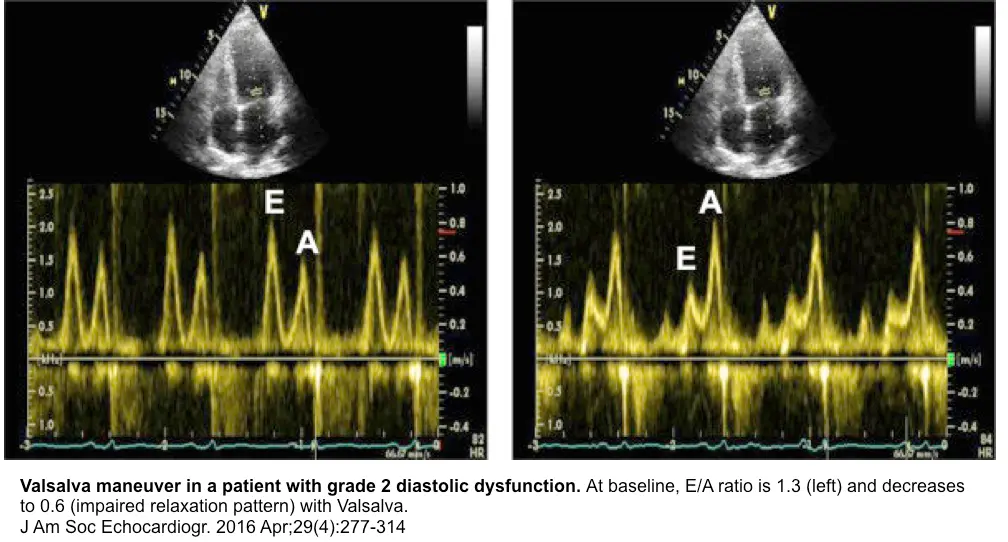

E/A ratio

- The E/A ratio in healthy, euvolemic, recumbent young adults is typically >1.

- The E/A ratio in healthy, euvolemic, recumbent young adults is typically >1. When τ is prolonged (often seen with aging, HTN, HCM, ischemia, AMI), is lower, and the E-wave is smaller, leading to the grade I diastolic dysfunction filling pattern where E/A <1.

- To compensate for impaired relaxation, LA pressure may rise, increasing and E-wave height, leading to the grade II (“pseudonormal”) or grade III (“restrictive”) diastolic dysfunction filling pattern, with consequent risk for pulmonary congestion

- Valsalva maneuver to tease out normal vs “pseudonormal” (grade II) diastolic dysfunction

- tbh, this is an old school 👵 approach, so you may rarely have a sonographer collect this for you

- normal: Valsalva → ↓ preload → ↓ amplitude of both the E- and A-wave

- grade II diastolic dysfunction: Valsalva → ↓ preload → filling will occur on the flatter portion of the LV diastolic PV relationship; ∴, E-wave amplitude ↓ > A-wave amplitude ↓ less (or may actually ↑) → E/A reversal (i.e., E/A ratio <1)